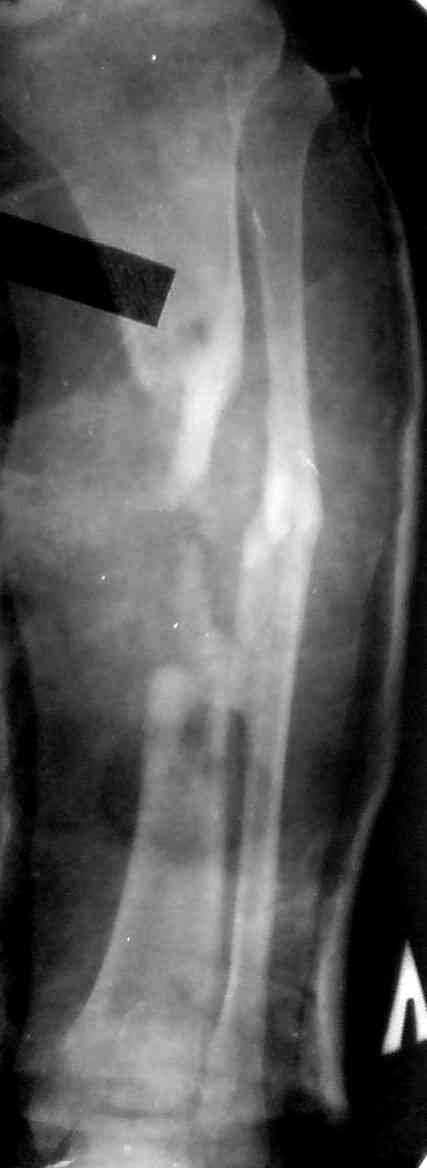

Как дополнение высылаю снимки и фото конечности, чтобы Вы могли оценить состояние м/т, и течение заболевания.

Кстати на предоперационных снимках видно, что Ваш пациент имел Сегментарный перелом на границе верхней и средней трети большеберцовой кости и средней трети большеберцовой кости. Непонятно почему был удалён средний сегмент перелома.Почему в течении такого большого времени не предпринимались попытки для замещения деффекта.

Судя по месту расположения свища, наличия литического учаска в проксимальной части дистального фрагмента на последнем снимке, и, наличие в этом месте стержня Шанца на послеоперацционном снимке, причина остеомиелита у Вашего пациента спицевая.